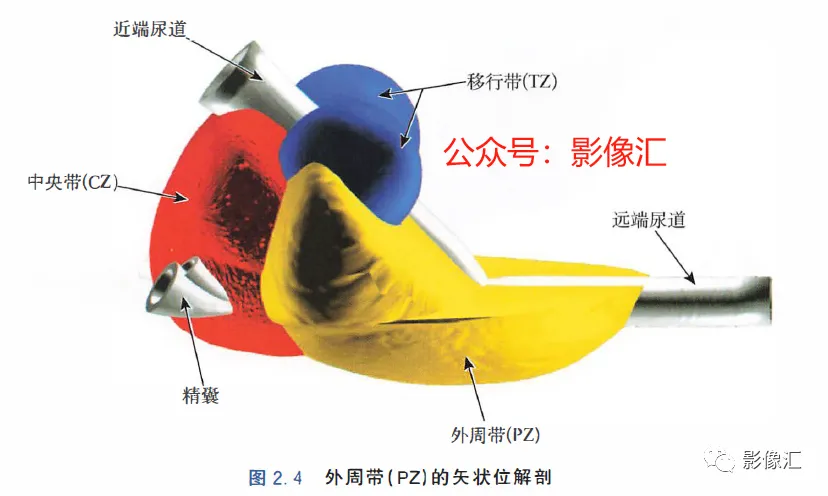

McNeal解剖模型认为前列腺根据周围不同结构环绕的关系而分为四个区域。尿道是描述整个前列腺区域解剖结构的解剖学标志。尿道由近端和远端尿道两个部分组成,每个部分约15mm长,由精阜分界。在精阜处,近端和远端尿道的走行呈35°。尿道壁由纵向走行的平滑肌纤维组成。围绕该内层的纵向肌肉层,是一层环形走行的肌层。两层平滑肌构成所谓的尿道内括约肌(IUS),其从膀胱颈延伸到尿道膜部的末端。IUS在膀胱颈的近端水平处最厚,随其向尿道膜部延伸,厚度逐渐减小。尿道膜部完整地被IUS环绕。在其前侧,前列腺内的lUS与前列腺肌性间质(AFMS)融合。两射精管走行方向与远端尿道平面平行,其开口于尿道腔内的前列腺小囊。移行带在前列腺组织中约占5%,构成两叶分别位于近端尿道两侧。其导管系统平行于尿道平面走行,止于精阜,射精管开口的近侧。移行带毗邻外周带,中央带和前列腺肌性间质,构成所谓的外科手术包膜,也就是说,确定了前列腺剜除术的外科手术平面。移行带和尿道周围腺体组织是良性前列腺增生(BPH)的发生部位。前列腺癌发生在移行带的比例为10%~20%。中央带在前列腺腺体组织中约占25%。其在前列腺底部形成金字塔形或锥形结构,在精阜水平处变窄至顶点。中央带的导管在射精管开口的两侧呈放射状走行。精囊和输精管穿入中央带形成射精管形似“精囊喙”。此区域由于缺乏前列腺包膜而成为解剖薄弱区。与射精管延续的中央带及伴行的筋膜和淋巴血管组织称为前列腺嵌入部(invaginated extraprostatic space,IES)。这是另一个解剖学上的薄弱区域,因此中央带疾病容易沿此区域播散。中央带相对发病率较低,发生在中央带的前列腺癌占5%~10%。外周带和中央带之间缺乏解剖学屏障,同时由于IES的存在,意味着前列腺尖部发生的肿瘤很容易进展到前列腺底部,并可早期造成前列腺周围间隙结构的受累。外周带约占前列腺腺体组织的70%。其包括前列腺表面的外侧、背侧和尖部,以多变的方式向腹侧延伸,与前纤维肌性间质相延续。前列腺不具有通常意义上的包膜结构,表面有一层腺样间质被称为“包膜"。前列腺“包膜”本身由纤维肌性间质构成,其在腺体周围形成一薄层结构。前列腺尖部没有这种间质层,造成一个解剖学上的蒲弱区域,称为梯形区域(trapezoidal area)。该区域腹侧以尿道膜部为界,背侧则以Denonvilliers和直肠筋膜为界,头侧以前列腺尖部(外周带)为界,尾侧则以直肠尿道肌为界。70%的前列腺癌发生在前列腺外周带。当前列腺癌起自前列腺尖部时,在早期即可通过梯形区域侵犯前列腺周围间隙。前列腺的背外侧神经血管蒂也是肿瘤易向外蔓延和侵袭的区域。AFMS约占前列腺体积的33%,是前列腺的非腺体区域,构成前列腺的前表面。在其最近端部分,其与逼尿肌和尿道内括约肌(IUS)的平滑肌纤维融合。头侧,其保持和尿道外括约肌(EUS)的关系;EUS的横纹肌纤维在该区域(前列腺尖部的前外侧)融合,构成前列腺外括约肌群。有四个“解剖薄弱“ 区域,通过这些区域,前列腺肿瘤可以生长并侵犯相邻的结构。这些区域是:精囊喙(图2. 6和图2. 17)

- 前列腺分为四个区域:移行带(TZ)、中央带(CZ) 、外周带(PZ) 和前列腺肌性间质带(AFMS)。

- 前列腺有三个“假包膜” :①Retzius前列腺周围包膜,与AFMS融合;②真正的包膜,腺样间质聚集;③外科手术包膜,由于BPH 导致AFMS、CZ 和PZ 受压而形成。